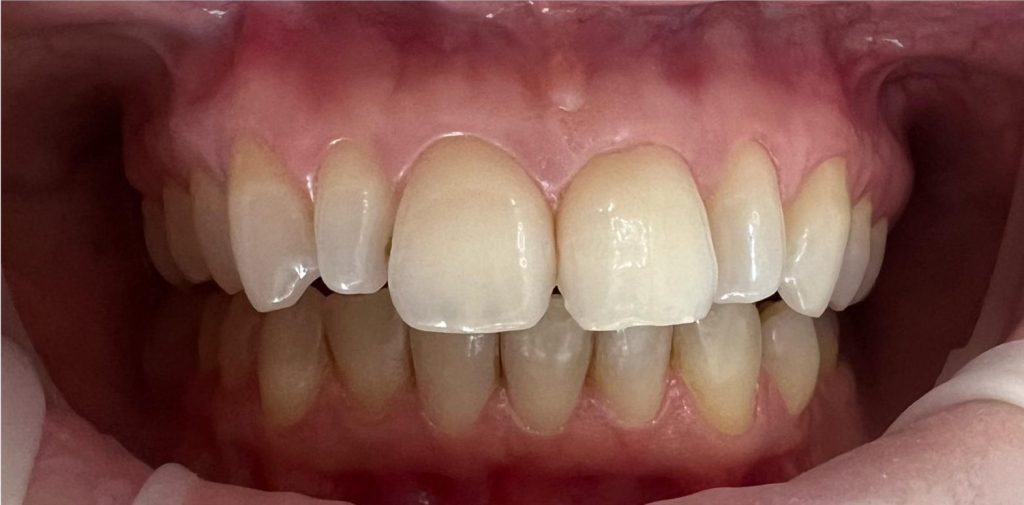

Aby osiągnąć taki efekt, musieliśmy przeprowadzić ekstrakcję złamanej górnej jedynki i w jej miejsce jednoczasowo wszczepić implant, a następnie na pozostałe zęby wykonać licówki i korony pełnoceramiczne w najjaśniejszym odcieniu.

Całość została zaprojektowana w harmonii z twarzą i rodzajem uśmiechu naszej Pacjentki. Leczenie trwało 3 miesiące.

Wykonał je lek.stom. Michał Badowski we współpracy z laboratorium Dentalscan (tech.dent. Joanna Gancarz).